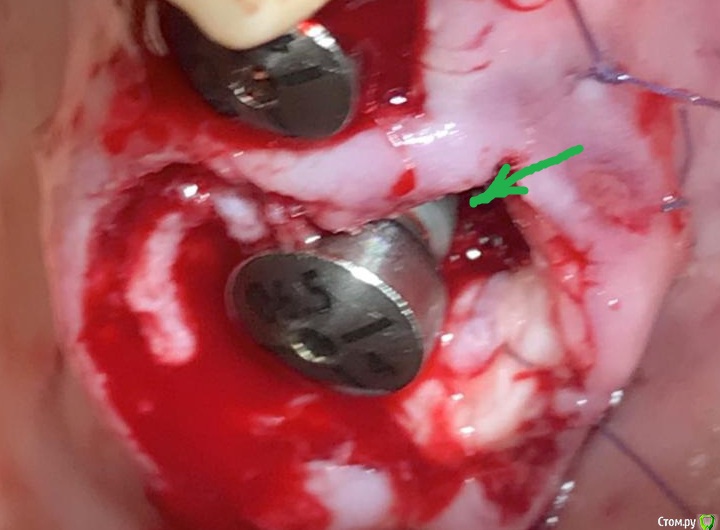

Дмитрий М Опубликовано 10 июля, 2019 Поделиться Опубликовано 10 июля, 2019 (изменено) спасибо, слежу за вашими работами на фб ) чем прикрыли край импланта? (зеленая стрелка) так понял графт не использовали? Изменено 10 июля, 2019 пользователем Дмитрий М Ссылка на комментарий

колесников Опубликовано 10 июля, 2019 Автор Поделиться Опубликовано 10 июля, 2019 Конечно использовал. Там лохань такая,имплант 5х11 только апексом заякорился. Сверху адгезивная повязка. Ссылка на комментарий

Дмитрий М Опубликовано 12 июля, 2019 Поделиться Опубликовано 12 июля, 2019 Конечно использовал. Там лохань такая,имплант 5х11 только апексом заякорился. Сверху адгезивная повязка.а какая именно адгезивная повязка, что используете? Ссылка на комментарий

колесников Опубликовано 12 июля, 2019 Автор Поделиться Опубликовано 12 июля, 2019 Жидкий коффердам-если 3-5 дней лунка ушита на формирователь. Жидкотекучий композит-если надо перекрыть на 7-10 дней Ссылка на комментарий